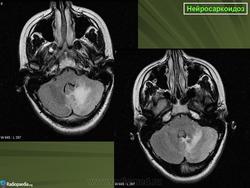

ID: 17921 Neurosarcoidosis Dr Frank Gaillard - 25 May 2012 The case demonstrates typical features of neurosarcoidosis, which are of...

Случай 1: с участием лептоменинга

Случай 2: с участием паренхимы

Случай 3

Случай 4: вокруг гипофизарного стебля

Случай 5: вовлечение спинного мозга

Случай 6: вовлечение гипофизарного стебля